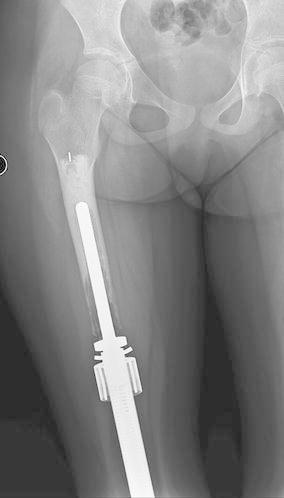

Limb-salvage for primary malignant bone tumors in pediatric patients presents a unique challenge when resection includes an active physis. Early expandable prostheses required open surgical procedures to achieve lengthening. Newer prostheses are capable of achieving expansion without open procedures through the use of an electromagnetic field. This study reports our results with 90 consecutive expansion procedures using the Repiphysis(®) prosthesis. We retrospectively reviewed the records of 20 patients (22 limbs) who underwent limb-salvage using the Repiphysis(®) prosthesis from 2003 to 2015. There were 9 males and 11 females with a mean age of 9 years and 9 months (6-16 years). Reconstruction included the distal femur in 11 cases, total femur in four, proximal tibia in three, proximal humerus in three, and total humerus in one. Complications were reviewed and functional scores were recorded using the MSTS/ISOLS system. Five patients had a second prosthesis implanted during the course of the study for a total of 27 prostheses. The mean follow-up was 57 (6-148) months. Four patients have not been expanded: three due to death prior to lengthening, and one patient who has not yet developed a leg length discrepancy. Ninety consecutive expansion procedures were performed in 18 limbs in 16 patients. A mean of 9 (5-20) mm was gained per expansion and 4.8 cm per patient who has undergone expansion to date. Seven patients have reached skeletal maturity and have been converted to an adult endoprosthesis. These patients averaged 8 expansions per patient and a mean of 7.4 (1.8-12.9) cm in length gained. There were 15 complications in 11 patients including one dislocation, one contracture, four cases of aseptic loosening, five structural failures (three expansion mechanism failures and two tibial fractures), three deep infections, and one case of local recurrence. The mean MSTS score was 80 % (37-97 %) and the limb retention rate was 95 %. The results of this study are comparable to previous studies involving non-invasive prostheses. This study hopefully provides additional data for clinicians to consider when faced with limb threatening sarcomas in the immature skeleton.

对于小儿原发性恶性骨肿瘤进行保肢手术时,如果切除范围包括活跃的生长板,会带来独特的挑战。早期的可扩张假体需要通过开放手术来实现延长。新型假体能够通过使用电磁场在不进行开放手术的情况下实现扩张。本研究报告了我们使用Repiphysis®假体连续进行90次扩张手术的结果。我们回顾性分析了2003年至2015年期间20例(22条肢体)使用Repiphysis®假体进行保肢手术患者的记录。其中男性9例,女性11例,平均年龄为9岁9个月(6 - 16岁)。重建部位包括11例股骨远端、4例全股骨、3例胫骨近端、3例肱骨近端和1例全肱骨。回顾了并发症情况,并使用MSTS/ISOLS系统记录功能评分。5例患者在研究过程中植入了第二个假体,共植入27个假体。平均随访时间为57(6 - 148)个月。4例患者未进行扩张:3例因在延长前死亡,1例尚未出现腿长差异。16例患者的18条肢体共进行了90次连续扩张手术。每次扩张平均增加9(5 - 20)mm,截至目前接受扩张的患者平均每人增加4.8 cm。7例患者已达到骨骼成熟并已转换为成人型假体。这些患者平均每人进行8次扩张,平均增加长度为7.4(1.8 - 12.9)cm。11例患者出现15例并发症,包括1例脱位、1例挛缩、4例无菌性松动、5例结构故障(3例扩张机制故障和2例胫骨骨折)、3例深部感染和1例局部复发。MSTS平均评分为80%(37 - 97%),肢体保留率为95%。本研究结果与先前涉及非侵入性假体的研究结果相当。本研究有望为临床医生在面对未成熟骨骼中威胁肢体的肉瘤时提供更多可供参考的数据。